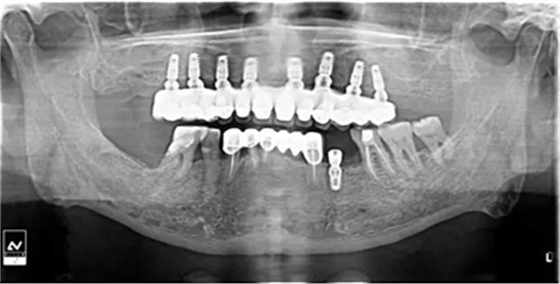

牙列缺失患者由于支持、固位、穩(wěn)定不足導(dǎo)致義齒效果差,如果在牙槽嵴內(nèi)植入種植體,種植體可以根據(jù)種植體數(shù)量不同提供義齒不同程度的固位、穩(wěn)定、支持,獲得不同的修復(fù)效果。當(dāng)單頜牙列缺失患者使用1-2顆植體,植體和覆蓋義齒之間可以靠一些附著體如磁性附著體、桿卡式附著體、球帽式附著體等裝置連接,主要提供固位和穩(wěn)定作用,少量的支持作用,當(dāng)單頜牙列缺失使用4顆植體時(shí),很大部分支持力可以由植體承擔(dān),當(dāng)使用4顆以上植體時(shí)可完全由種植體提供義齒的支持、固位和穩(wěn)定,甚至制作為不可摘戴的全口固定種植義齒。